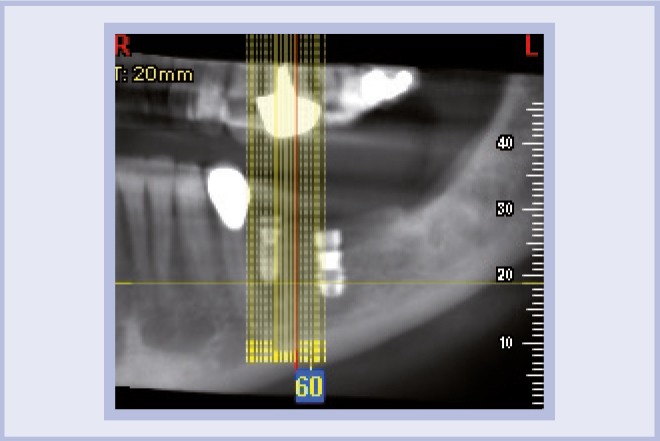

Per riabilitare la masticazione del terzo quadrante, con osso gravemente atrofico, si procede allo studio del caso con esame radiologico 3D e posizionamento virtuale di impianti Exacone® Leone. La prima valutazione è stata eseguita con il software dell’apparecchio radiografico Cone Beam presente in studio. Dopo aver verificato che la quantità di osso residuo fosse sufficiente all’inserimento di due impianti, seppur di dimensioni ridotte, in sede 3.5 e 3.6 senza l’ausilio di tecniche di rigenerazione ossea (Figg. 1-3), si richiede al laboratorio di confezionare una mascherina radiologica con ceratura diagnostica radiopaca e repere standardizzato a livello incisale come da protocollo Leone (Figg. 4, 5). Si verifica quindi clinicamente l’assenza di mobilità della mascherina dopo il posizionamento nel cavo orale del paziente (Figg. 6, 7). Si effettua una CBCT con la mascherina in posizione e l’esame viene inviato in formato DICOM all’azienda Leone assieme al modello master della paziente. L’azienda provvede quindi ad inviare agli Autori il software 3Diagnosys (software di progettazione) in licenza monopaziente con caricati i file DICOM ricevuti; il software viene quindi utilizzato per la progettazione definitiva del caso (Figg. 8-12).

- Figg. 1-3 – Esame Cone Beam iniziale, si verifica la fattibilità di inserimento impianti

- Fig. 2 mento impianti

- Fig. 3